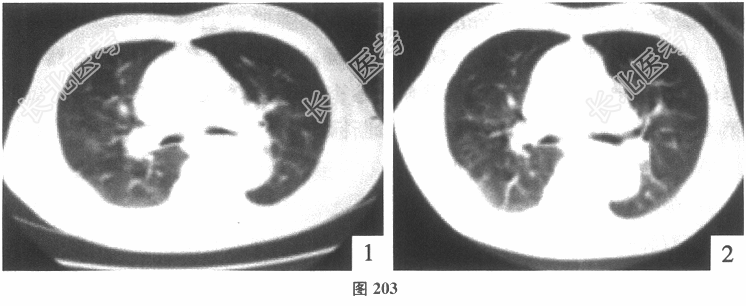

- 多项选择题2.[提示]患者胸部CT检查:示双肺弥漫性磨玻璃样片状影(图203)。目前考虑患者的诊断可能是( )